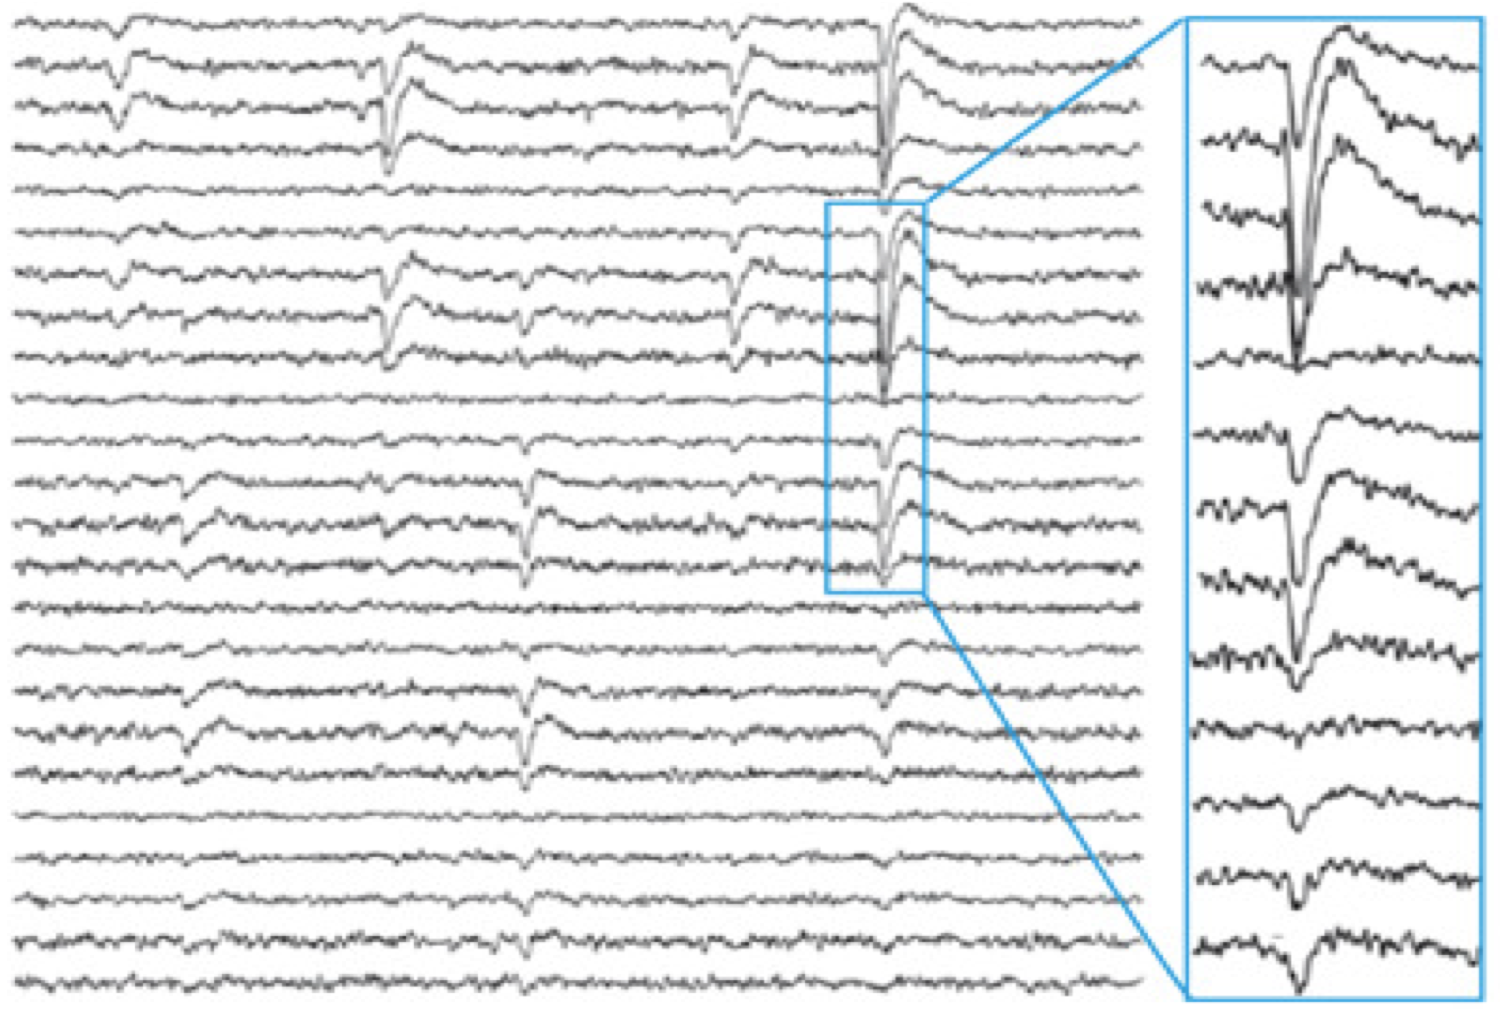

Neuronal Avalanches: What are They and What do They Mean?

Neuronal avalanches are a structure of organization of cascades of synchronized of activity in the cortex that have several surprising implications for how we understand…